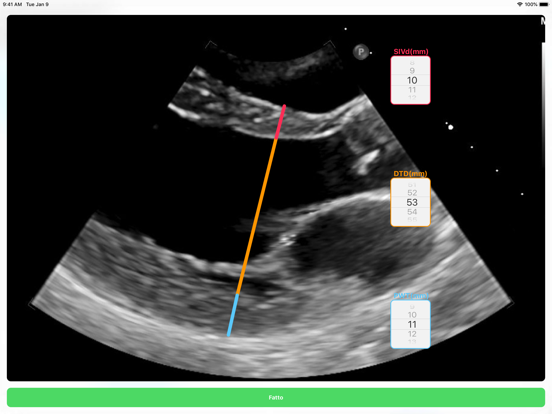

Con l’esame ecocardiografico è possibile stimare la massa del ventricolo sinistro e determinare lo spessore relative delle pareti.

L' app consente in tempo reale di determinare il pattern di geometria del ventricolo sinistro.

• Screenshot #1 pour LVG Calc

• Screenshot #2 pour LVG Calc